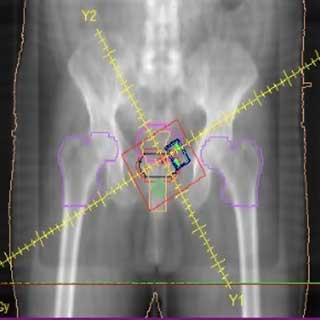

Esto significa que, desde la primera consulta, el Dr. Salinas evalúa a fondo su caso: revisa su diagnóstico, estado de salud general y cualquier otra enfermedad concurrente. Luego, en colaboración con físicos y dosimetristas médicos, crea un plan de tratamiento personalizado que maximice el impacto en el tumor y reduzca el riesgo para el resto del cuerpo